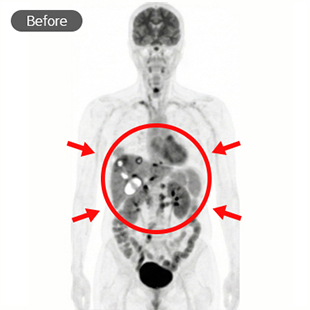

현재상태 2025. 05 ~ , 현재NED(암 병변 없음) 8개월차 / 재발방지치료 중

대학병원 항암화학요법 - FOLFOX

리움한방병원 싸이모신알파원, 미슬토, 고용량셀레늄, 고주파온열치료(BSD-2000), 항암단, 건칠정